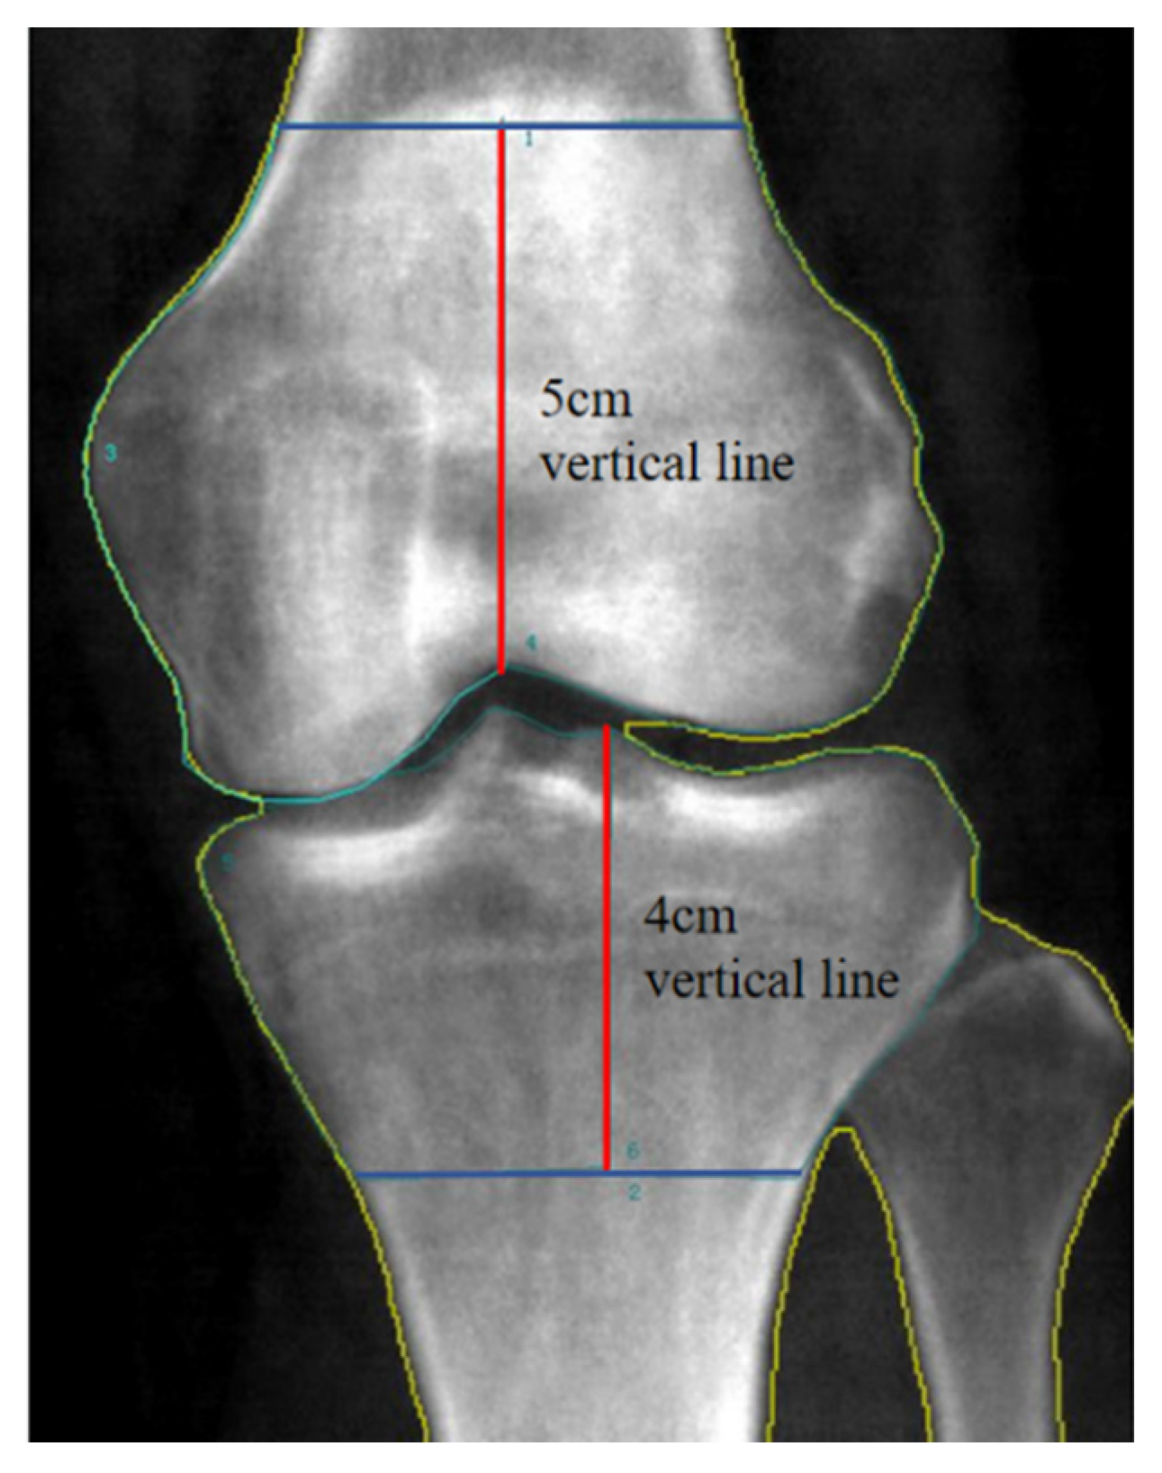

- Lateral Condyle Cancellous Bone HU Value: We drew a 5 cm vertical line upward from the highest point of the intercondylar fossa, avoiding the cortical bone, and measured within the fixed region (Figure 2B).

- Medial Condyle Cancellous Bone HU Value: We drew a 4 cm vertical line downward from the lateral intercondylar eminence, avoiding the cortical bone, and measured within the fixed region (Figure 2F).